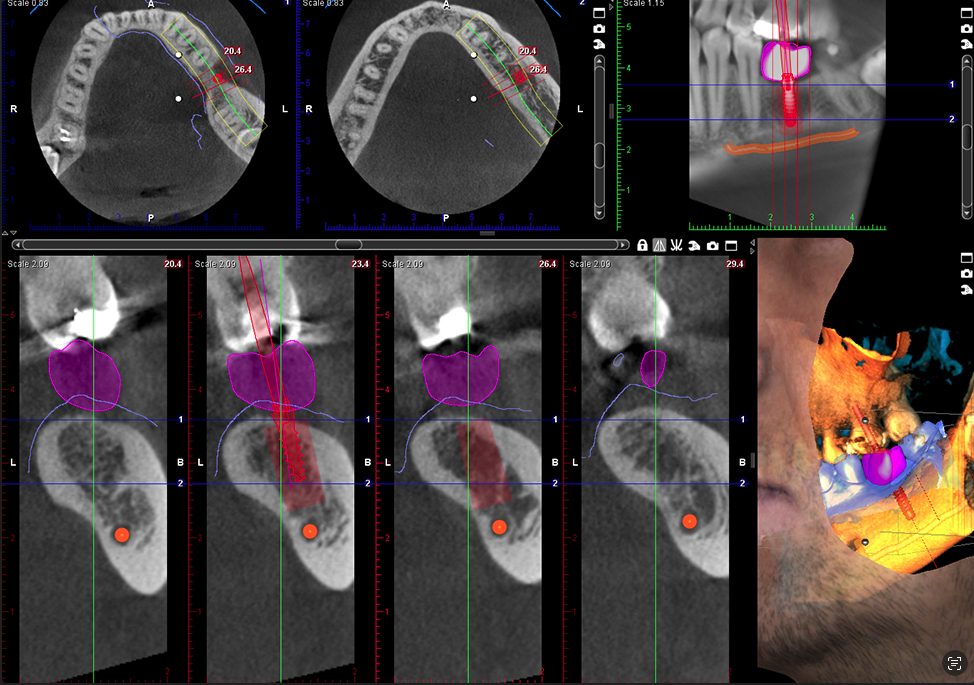

Canino impactado

Volumen 8 x 8

Implante con corona